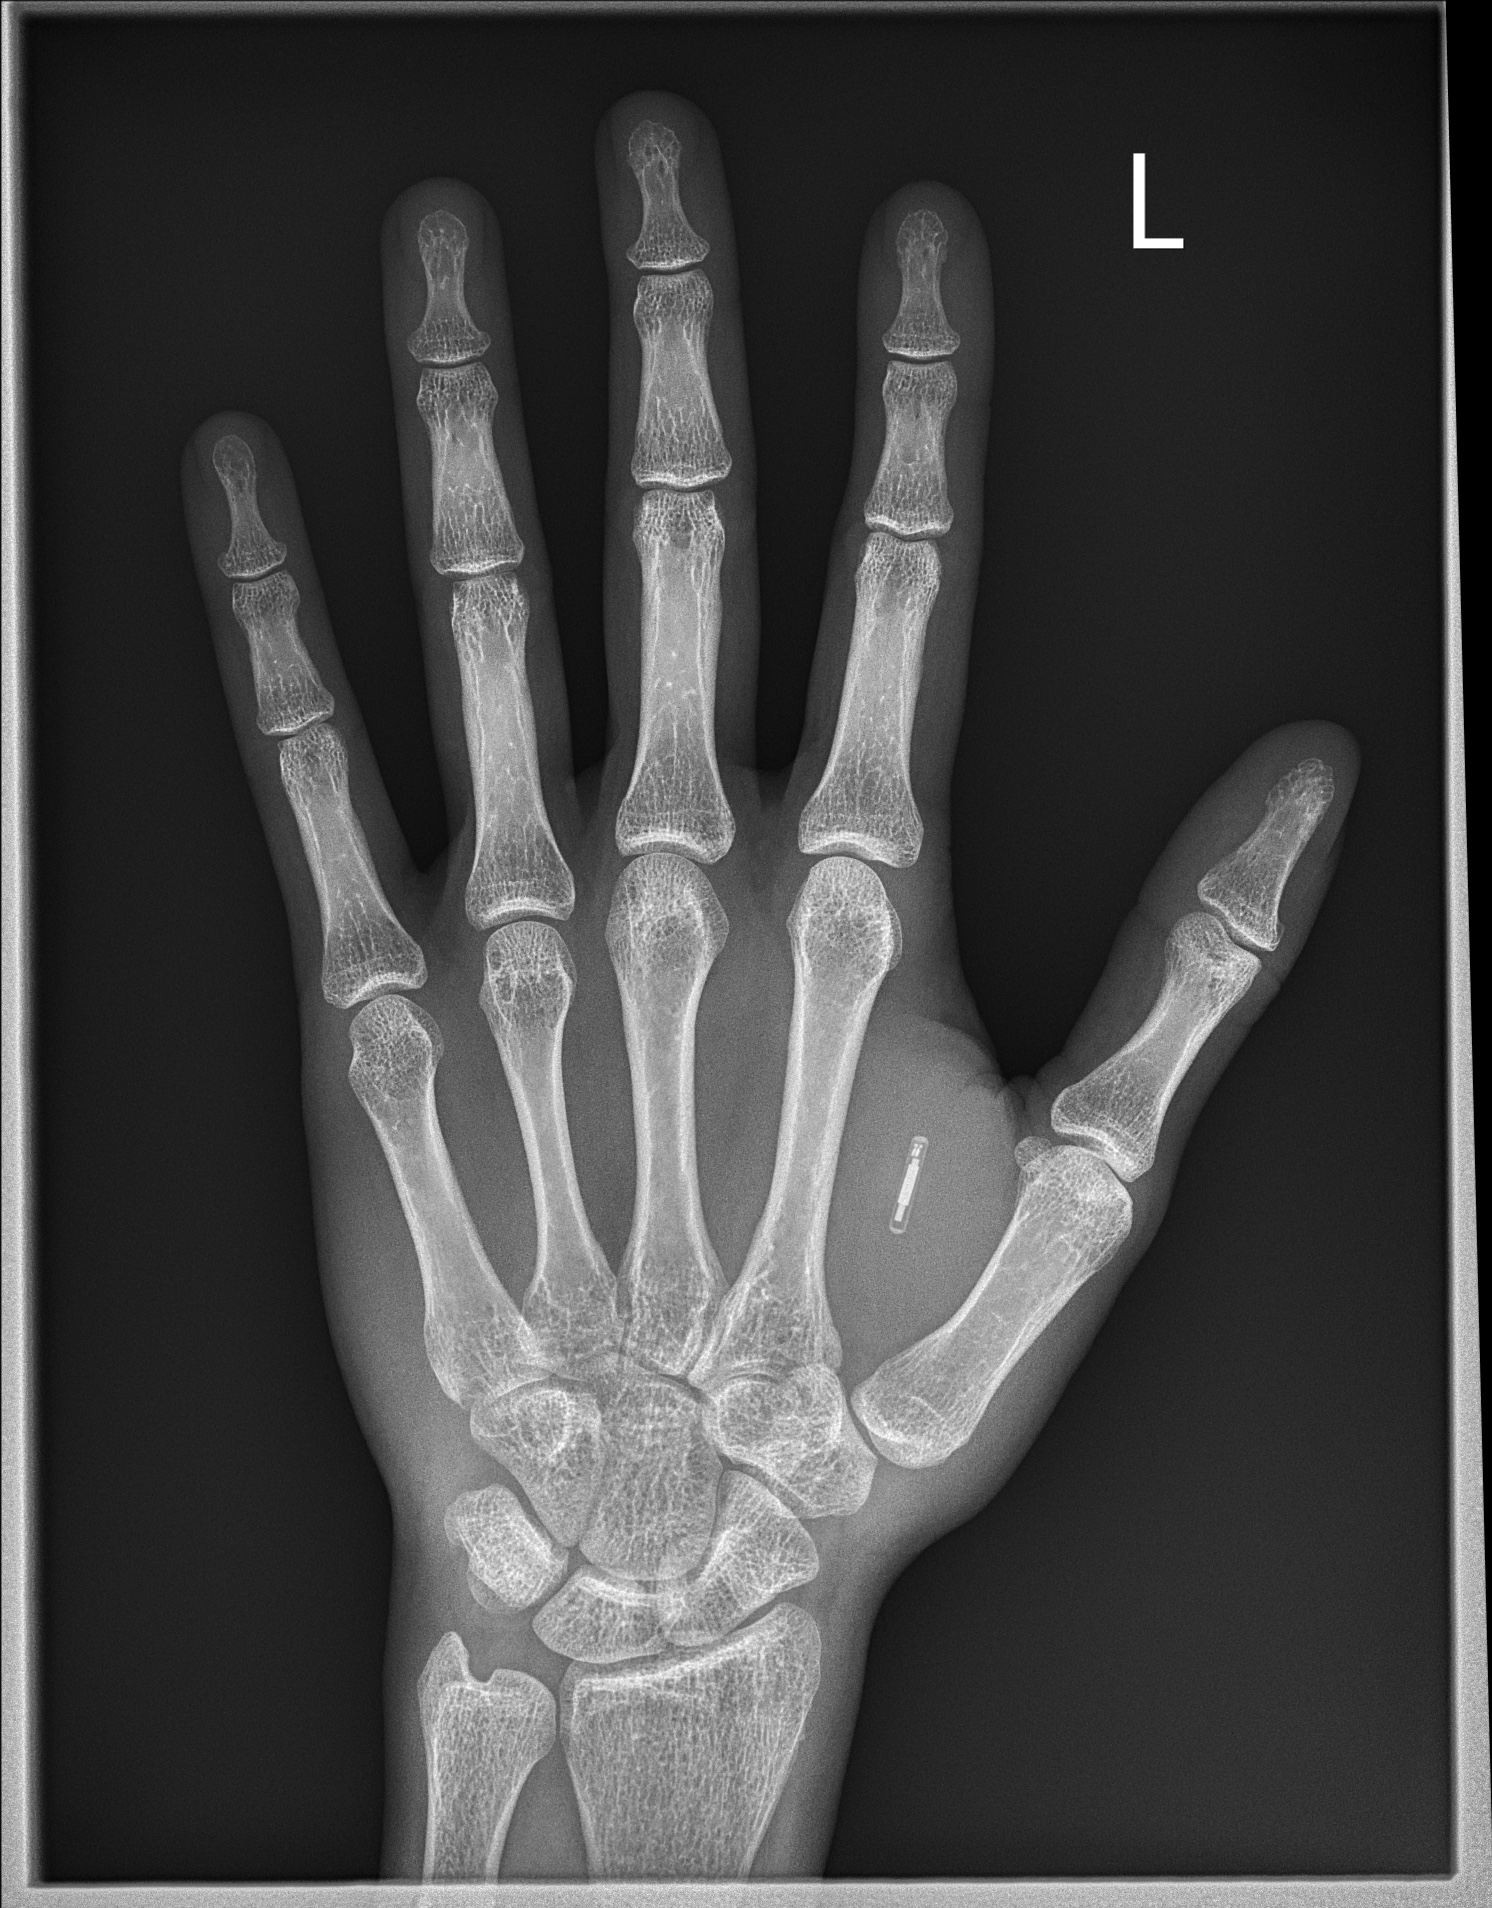

Tak faktycznie, chodzi o rozwiązanie inwazyjne, wymagające wprowadzenia takiego chipa pod skórę. Mogłyby one jednak spełniać wiele funkcji, uzasadniających potencjalnie taką ingerencję, na przykład stanowić alternatywę dla środków antykoncepcyjnych, co potwierdzają badania przeprowadzone przez naukowców z MIT. Od zeszłego roku jest też głośno o polskim startupie Walletmor. Producent oferuje chipy płatnicze mające niecałe 3 centymetry długości, które również wprowadza się pod skórę. Gdyby cofnąć się o kilka lat, do 2014 roku, to chipy cieszyły się też sporą popularnością wśród Szwedów. Umieszczano je w dłoni, aby zastąpić w ten sposób np. klucze czy bilety kolejowe. Aktualne dane sugerują, że w Szwecji zaczipowanych jest około 6 tysięcy osób, jednak dynamika tego zjawiska zdecydowanie spada.

Pojawił się również aspekt potencjalnej manipulacji i sterowalności naszymi decyzjami czy zachowaniami. Wydaje się, że to kwestia, która może być wynikiem trwającej pandemii i potencjalnej obawy, że w przyszłości w imię np. bezpieczeństwa społecznego, na podstawie danych zapisanych na chipie, ktoś mógłby decydować o przysługujących nam przywilejach. Poza tym, ważnym elementem okazały się również kwestie zdrowotne, ponieważ proces chipowania wymaga rozcięcia skóry i umieszczanie pod nią tego typu urządzenia. Można też sobie wyobrazić scenariusz, w którym kolejne chipy mają coraz to nowe funkcjonalności, podobnie jak obecnie projektowane smartfony. W takiej sytuacji pojawia się, z czasem, konieczność wymiany tych urządzeń, co wiązałoby się z dalszą ingerencją w nasze ciało. Może to być sygnał dla producentów, że warto byłoby rozważyć dalszą miniaturyzację chipów oraz maksymalne wydłużenie ich żywotności.

Być może właśnie z tego względu zaledwie 5 procent badanych wyraziło chęć implementacji takiego chipa. Ankietowani byli bardziej otwarci na chipy oferujące znacznie większe spektrum możliwości, a nie tylko ograniczające się do wykonywania płatności. Może się okazać, że jeśli powtórzymy te badania za kilka lat, to oczekiwania społeczeństwa względem chipów będą diametralnie różne. Obecnie największe zainteresowanie wzbudzały obszary związane ze zdrowiem, na przykład wykonywanie pomiarów temperatury ciała, ciśnienia krwi czy stężenia glukozy. Wskazywano też na przechowywanie danych medycznych, takich jak leki przyjmowane przez posiadacza chipa, choroby przewlekłe na które cierpi czy też informacje o grupie jego krwi.